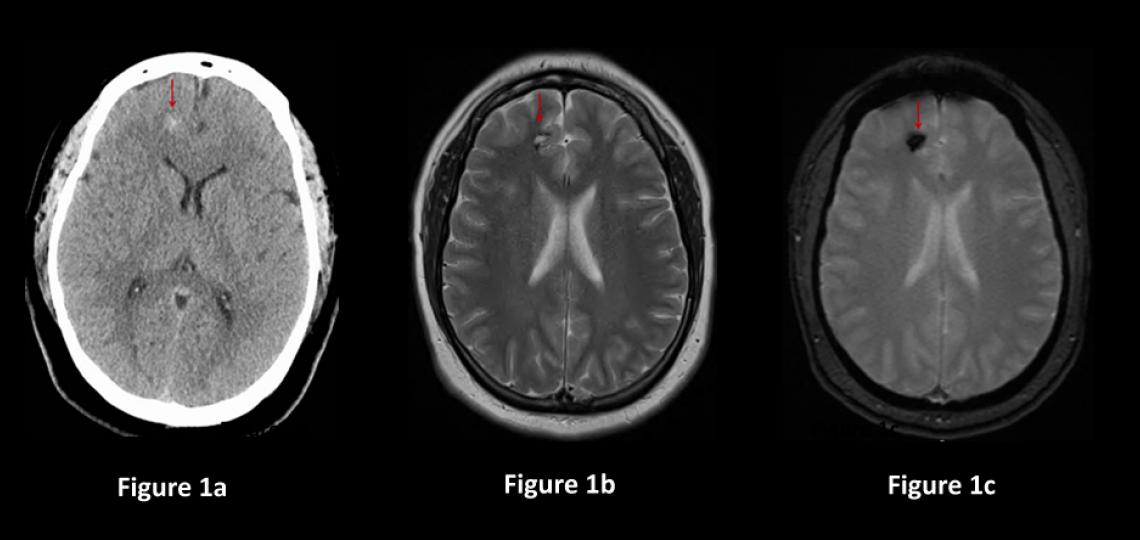

Generally, cavernous malformations that are small, not causing symptoms or located in critical brain areas are not treated immediately but rather monitored (Figure 1). Most such patients are "followed" by repeat MRI scan every year for several years, then if there is no growth, the MRIs are spaced out every two to five years after that. Treatment may be needed if the lesion grows or causes new symptoms.

Figure 1a: CT scan of the brain in a patient with a mild headache showing a small spot of white bleeding (red arrow). Figure 1b: Brain MRI scan showing a small cavernous malformation (red arrow) in the frontal lobe. Figure 1c: Brain MRI sequence showing the presence of bleeding (red arrow).